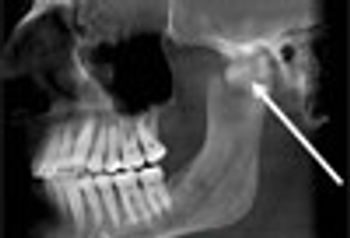

A 62-year-old man with a persistent snoring problem presented for an oral medicine consultation. There was no history of jaw trauma or jaw fracture; jaw function was normal and the patient was not in pain.